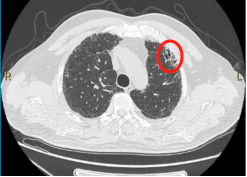

今年68岁的李大伯,平时身体健康,2019年做胸部CT时,发现双肺少许间质性肺炎改变,因为没有出现咳嗽、咳痰、气促等症状,李大伯对此并未在意。2023年11月开始,李大伯出现轻微咳嗽,于是再次进行体检。胸部CT显示,双肺间质性肺炎病变较前增多、进展,进一步查肺功能显示限制性通气功能障碍、弥散功能中度下降,李大伯这下慌了,遂来我院接受进一步检查。

▲2019年胸部CT显示,少许间质性肺炎

(画圈处)改变

▲2023年胸部CT显示,双肺间质性肺炎

(画圈处)病变较前增多、进展

通过完善自身免疫抗体筛查、气管镜检查等,同时经呼吸与危重症医学科、风湿免疫科、放射科等间质性肺疾病多学科讨论,最终诊断“特发性非特异性间质性肺炎”。李大伯在接受口服抗炎、抗纤维化药物治疗后,并定期评估肺功能及胸部CT,目前评估病情逐渐改善。